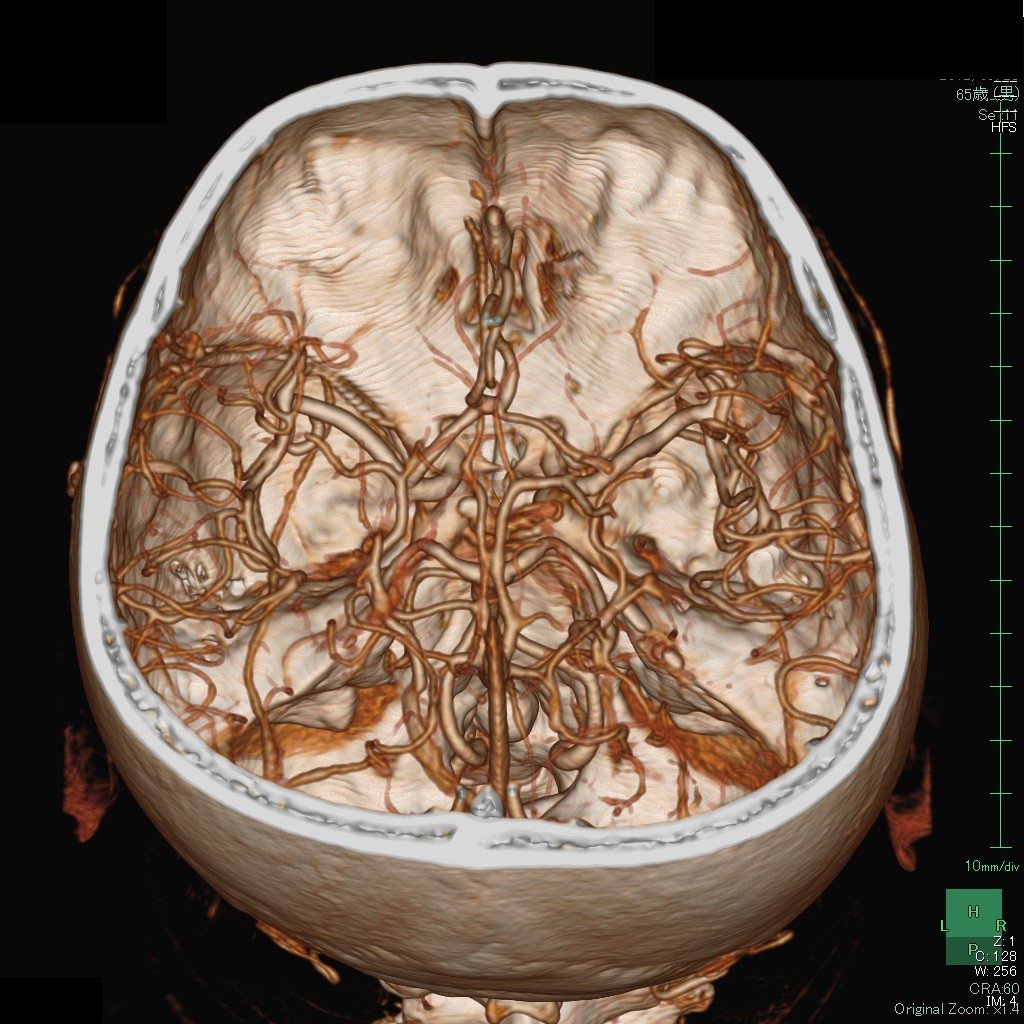

これは、造影剤を使って脳内の動脈を3Dで撮影した画像(3D-CTA)です。患者さんに説明するときにも、画面でmovieとしてお見せできます。

たとえば、このYouTubeの画像は私が血管内治療をする直前の3D-CTAの画像(動画)です。

さらに、この3DーCTA画像は骨をどこで切り取るかによって色々な画像を作る事ができます

また、頭蓋骨ごと回転させて、頚部動脈も観察する事ができます